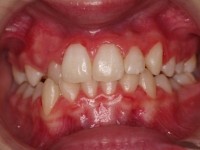

El paciente A.J. de 11 años, acude a nuestra consulta con apiñamiento maxilar importante. El canino lateral (12) está en mordida cruzada. Presenta una Clase II molar y canina, y la línea media está desviada. Se realizó un tratamiento con brackets autoligables metálicos de smartclip 022. La duración del tratamiento fue de 22 meses.

El paciente actualmente ha terminado el tratamiento con brackets y lleva una contención fija de 2-2 en maxilar y 3-3 en mandibular; para complementar también lleva una férula ESSIX durante la noche.

INICIO FINAL